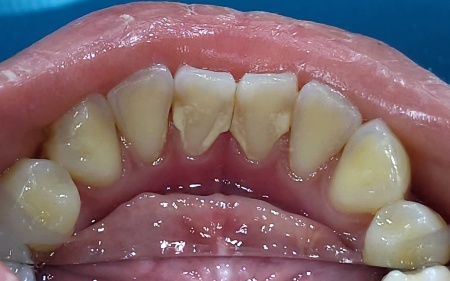

18歳女性 下前歯の裏側に付着した歯石を保険診療内のクリーニングで除去した症例

- 歯石除去

- クリーニング

- 予防歯科

- 治療期間の目安 -

- 治療回数の目安 1回

- 治療費総額の目安 保険診療内

治療のリスク

・病状、症状、患者様のお口の環境によって、複数回にわたる施術が必要となる場合があります ・治療が終わった後も、十分なセルフケアが必要です ・正しいブラッシングやメンテナンスを行わない場合、歯石の付着や虫歯が生じる可能性があります...

by.エスペレ歯科・ホープデンタルクリニック